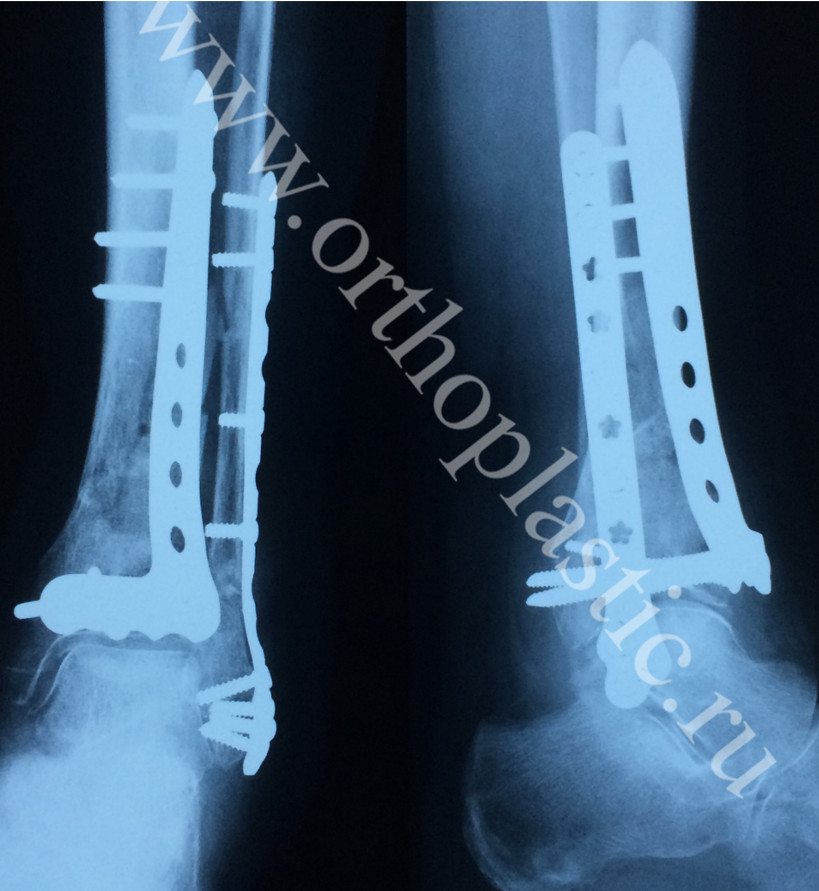

Рентгенограмма пациентки Р. 76 лет. Оскольчатый перелом обеих костей левой голени. Состояние после остеосинтеза пластинами.

Осложнение: некроз кожных лоскутов, инфицирование, обнажение пластины.